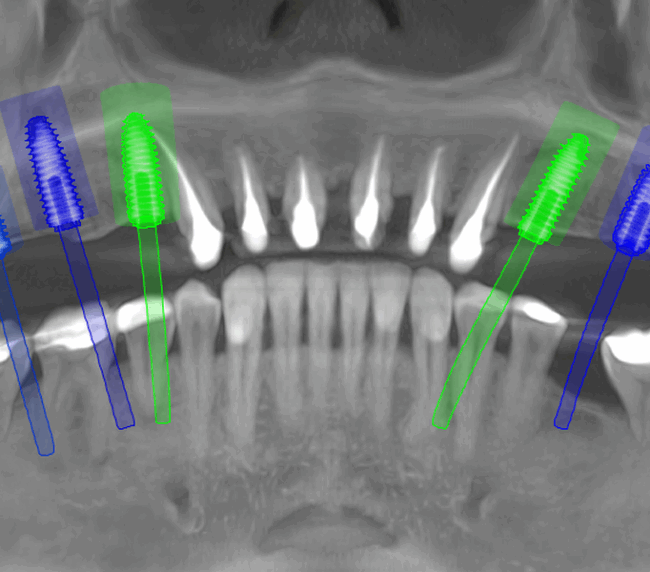

Reabilitarea complexă în stomatologie presupune refacerea completă a sistemului dentoalveolar, atât din punct de vedere funcțional, cât și estetic. Procesul începe cu o examinare detaliată a cavității bucale, interpretarea investigațiilor imagistice (CBCT), evaluarea musculaturii, articulațiilor temporomandibulare și a parametrilor estetici.

Tomografii (CBCT)

Caz 2